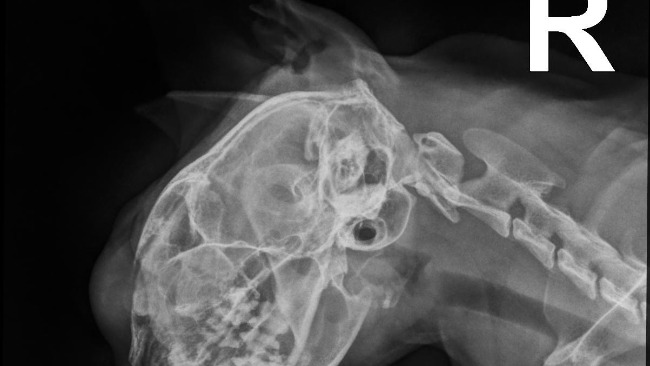

Niestety, dwa miesiące temu choroba Renii zaczęła postępować. Felv sprawił, że na jej pyszczku pojawił się duży chłoniak, który przeszkadza jej w normalnym funkcjonowaniu. Renia przestała jeść, pić i traci swoją radość życia. Potrzebuje teraz regularnych kroplówek, wizyt u weterynarza i dalszych badań. Każda opinia specjalistów jest inna, ale nie poddajemy się. 🥹

Koszt leczenia, które mogłoby zahamować rozwój choroby, to około 2200 zł. Zbieramy środki na dalsze diagnozy, badania kontrolne i niezbędne suplementy, aby dać Renii szansę na powrót do zdrowia. 😞